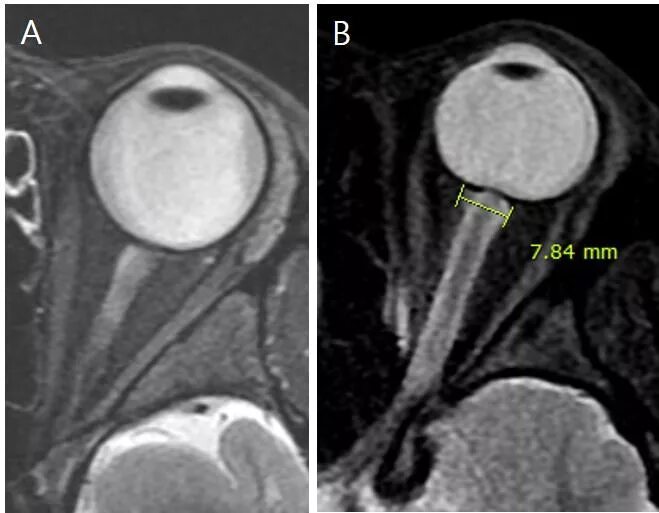

Субарахноидальное пространство зрительных нервов